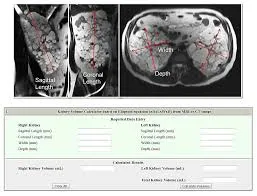

Quando diagnosticamos um paciente com Doença Renal Policística Autossômica Dominante (DRPAD) é fundamental classificar o prognóstico do paciente calculando o volume renal total (total kidney volume, TKV). Nesse vídeo explicamos como realizar e interpretar essa classificação!

Valkercyo Feitosa